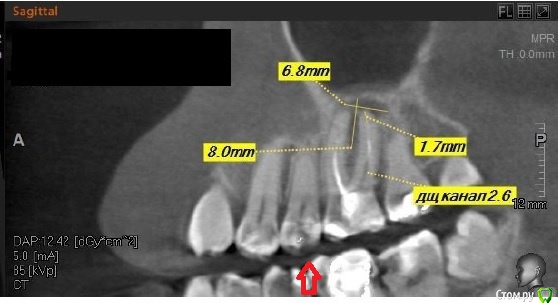

alex0814 Опубликовано 21 марта, 2015 Поделиться Опубликовано 21 марта, 2015 Здравствуйте! Сложилась непонятная мне ситуация. Зуб 2.5, живой, не болит. Заметно потемневший с одной стороны – но потемнение появилось еще лет 15 назад, после установки в этот зуб металлической пломбы.В описании недавнего трехмерного КТ снимка рентгенолог пишет: «2.5-витальный. Состояние после лечения кариеса на окклюзионной поверхности, восстановлен пломбой. Без изменений в периодонте и периапикальных тканях».В то же время, терапевт по результатам осмотра настоятельно рекомендует вскрывать и лечить, предполагает как минимум кариес. Ссылка на комментарий